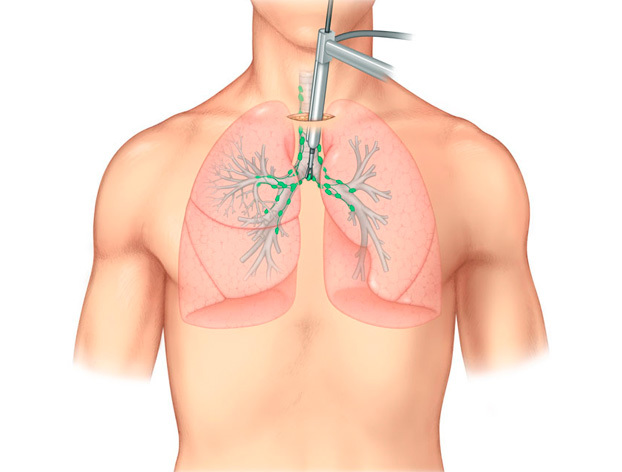

- Исследование при помощи бронхоскопии. Данное исследование более эффективное, чем обычная рентгенография. Поскольку основывается оно на непосредственном введении специальной гибкой трубки со встроенным объективом в бронх. И таким образом обследуется бронхи при развитии раковой опухоли можно наблюдать сужение и изъявление, стенки его смещаются в сторону и поддаются деформации.

- при проведении бронхоскопии — осмотра слизистой бронхов с помощью специального инструмента (бронхоскопа);

Внешний осмотр дыхательных путей, при котором оборудованием служит тонкий зонд из оптоволокна. Его вставляют через носовую или ротовую полость, и специалист имеет возможность продвигаться по всей дыхательной системе. Считается основной методикой диагностирования онкологии в легких.

Достоинство методики состоит в том, что с его помощью можно изучить, как выглядит новообразование внутри, провести исследования всех главных дыхательных путей. С помощью бронхоскопии можно провести морфологически подтвердить диагноз, изучить структуру злокачественного новообразования.

Биопсия с помощью бронхоскопа проводится во время бронхоскопии или медиастиноскопии. Используется, если есть подозрения на инфекцию или онкологию. Бронхоскоп вводится через ротовую или носовую полость.

Бронхоскопия

Бронхоскопия является диагностическим мероприятием, которое основывается на визуальном исследовании системы дыхании при помощи оптоволоконного зондирования. Зонд вводится в пути дыхания – при легочном раке бронхиальный просвет сужается и в нем развиваются язвенные процессы.

Также происходит деформация и смещение бронхиальных стенок. Могут также увеличиваться трахеобронхиальные лимфатические узлы.